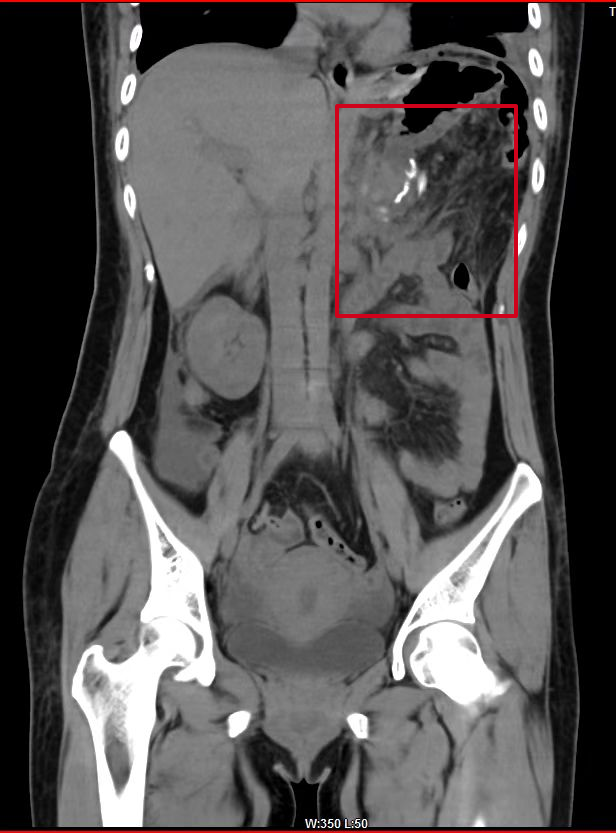

術後(hòu)複查CT提示:

巨大腫瘤已被(bèi)切除